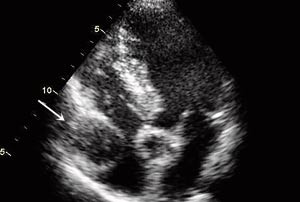

Transtorakal ekkokardiografi viste en veggfast homogen tumor, ca. 3,8 x 3,8 cm, lokalisert lateralt i høyre atrium like overfor tricuspidalklaffeplanet, samt et atrieseptumaneurisme (fig 2). Transøsofageal ekkokardiografi viste i tillegg en atrieseptumdefekt med både høyre-venstre- og venstre-høyre-shunt. Det ble ikke påvist blodstrøm i selve tumoren ved undersøkelse med fargedoppler.

Pasienten ble henvist til regionsykehus med tanke på videre diagnostikk. Koronar angiografi viste ektatiske koronararterier uten signifikante stenoser (fig 3). MR av hjertet viste en solid rundaktig oppfylning på ca. 3,7 x 3,3 cm som lå like innenfor perikard, omringet av epikardialt fettvev. Største del av oppfylningen buket inn mot høyre atrium og hadde nær relasjon til tricuspidalklaffen og proksimale del av høyre ventrikkel. Den tentative diagnosen etter disse tilleggsundersøkelsene var hjertetumor eller aneurisme i en av koronararteriene.

Funn av patologiske strukturer i furen mellom høyre atrium og høyre ventrikkel ved ekkokardiografi bør gi mistanke om aneurisme i høyre koronararterie. Mistanken om at vår pasient kunne ha et slikt aneurisme, ble forsterket etter at koronarangiografi viste ektatiske koronarkar, siden aneurismer og ektasier ofte foreligger samtidig.